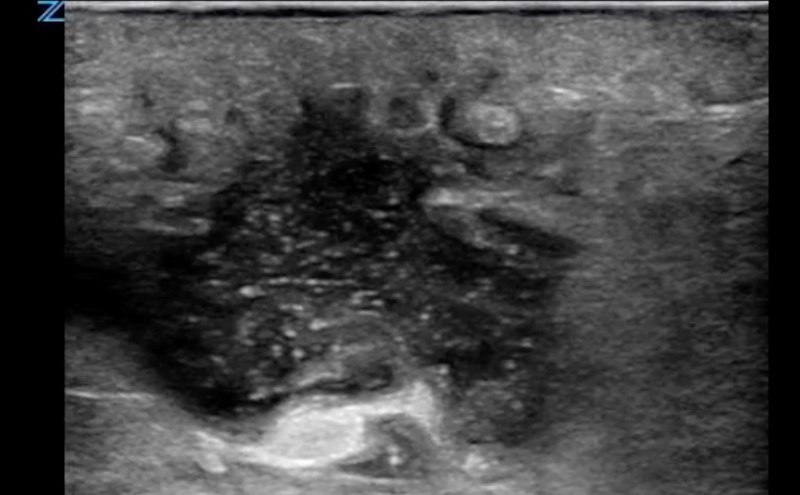

- On ultrasound, an abscess is a spherical or oblong structure that is largely anechoic or hypoechoic.

- Figure 2. Abscess containing hyperechoic debris

- However, as opposed to a simple cyst that will be uniformly anechoic throughout, an abscess will contain hyperechoic debris. This feature can be used to differentiate an abscess from a cyst.

- The walls of the abscess cavity might be distinct and hyperechoic, or they might have a ragged appearance and intermix with the adjacent tissue. Because of the anechoic nature of the abscess, posterior acoustic enhancement might be seen.

- Dynamic scanning, achieved with gentle compression of the probe, might cause the contents of the abscess to swirl, which can be diagnostic of an abscess.